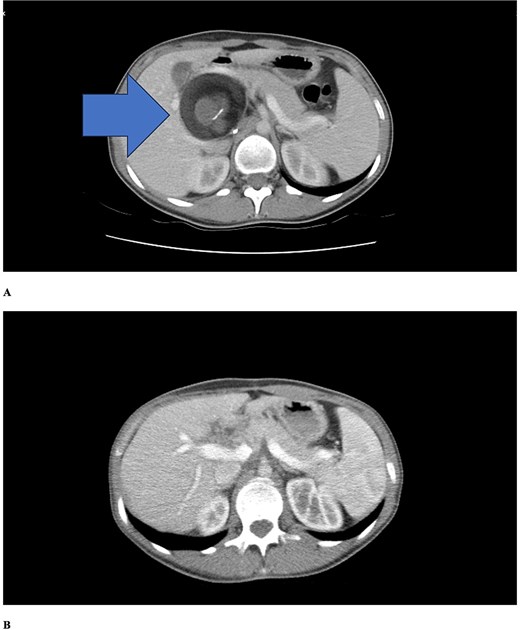

Abdominal computed tomography (CT) demonstrated a 4–5 cm cystic lesion in the hepatoduodenal ligament (Fig. 1a) containing fat density and fluid without calcifications. No biliary dilatation, cholecystitis, or vascular compression was seen. The gallbladder was normal. The liver was slightly enlarged with normal contours. Minimal intrahepatic bile duct prominence was noted.

Contrast-enhanced axial CT scans. (a) Preoperative imaging showing a well-defined cystic lesion in the hepatoduodenal ligament region with heterogeneous attenuation including areas of fat density (negative Hounsfield units) and fluid components. (b) Six-month postoperative follow-up demonstrating complete resolution of the lesion with no evidence of recurrence. Periportal millimetric metallic densities representing surgical clips are visible.

Postoperative course was uncomplicated. Intravenous antibiotics continued 48 h, then oral antibiotics for 7 days total. She was discharged on Day 4. At six-month follow-up, she remained asymptomatic with normal alpha-fetoprotein. Follow-up CT (Fig. 1b) showed complete resolution without recurrence, normal liver and bile ducts, and surgical clips in the periportal region.